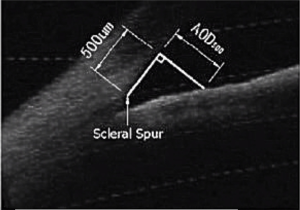

Scleral spur

Scleral spur, a narrow stenosis composed of circularly oriented collagen bundles, protrudes into the anterior chamber. It is an important and constant landmark usually used to determine the opening of the anterior angle, which previously needed to be identified manually. In OCT images, scleral spur is the location where the corneal curvature changes dramatically (Figure 1). The plane of the scleral spur is relatively parallel to the section of the corneal apex of the human eye. Thus, the plane of the scleral spur is a good benchmark for determining the IOL tilt. Canny algorithm was used to identify the scleral spur. After removal of the signal noise in the preprocessing procedure, the image was enhanced to highlight the posterior surface of the sclera. We then connected the scleral spur on each side with a line. The recognition effect of the algorithm is shown in Figure 2.